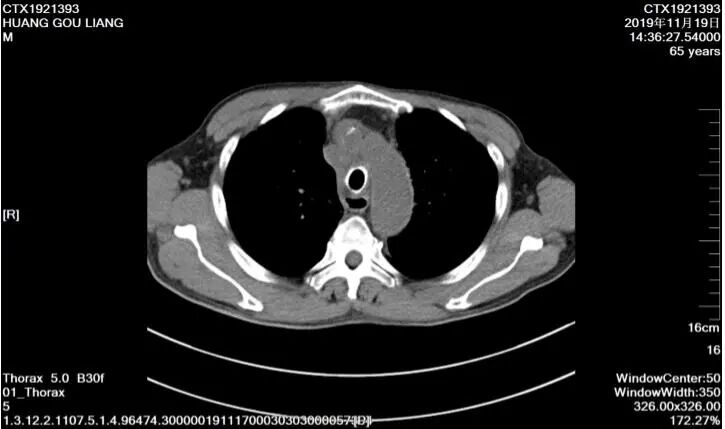

55歲男性,左肺鱗癌,行三次左肺支氣管動(dòng)脈灌注化療+栓塞術(shù)后,治療縮小,結(jié)合局部放療,病情控制可。

65歲肺鱗癌患者,縱膈淋巴結(jié)腫大擠壓食道導(dǎo)致無(wú)法進(jìn)食,放置食道支架后,恢復(fù)飲食并帶瘤生存。